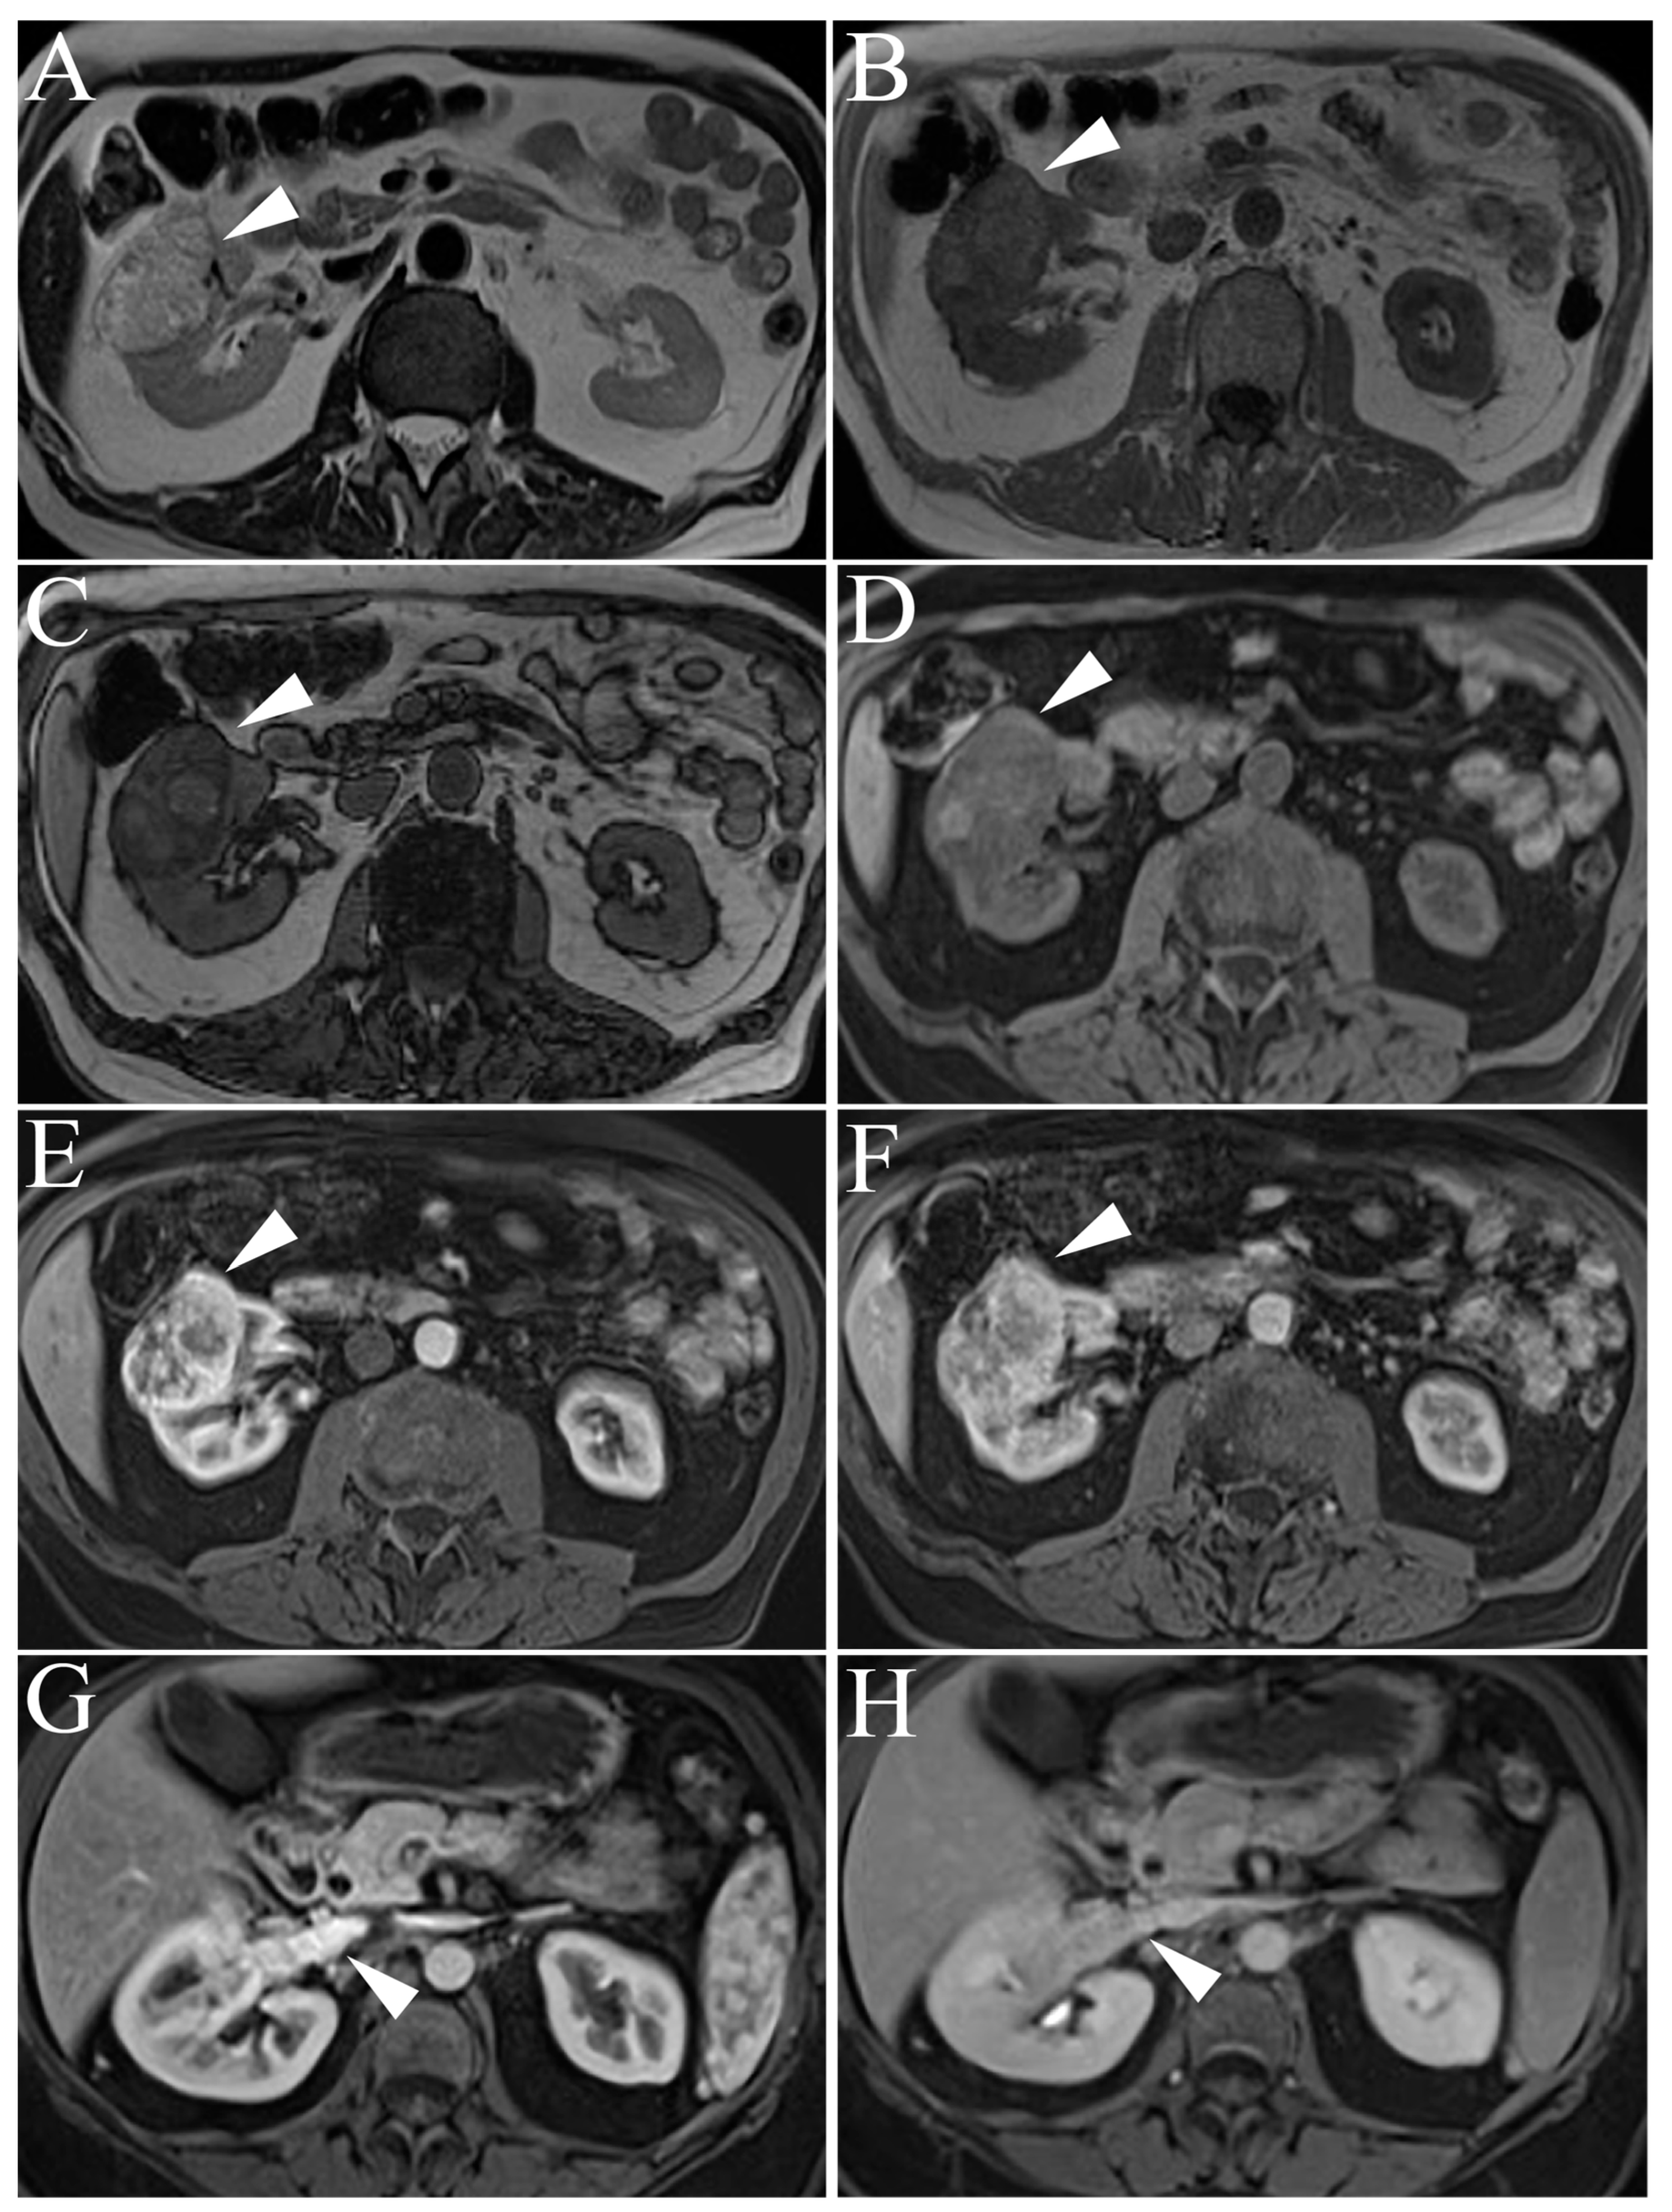

5.2. Papillary Renal Cell Carcinoma

5.3. Chromophobe Renal Cell Carcinoma

| Type 1 Papillary RCC | T2-hypointense Uniform progressive delayed enhancement Well-circumscribed, homogenous, peripherally-located |

| Type 2 Papillary RCC | Heterogenous T2 signal intensity Heterogenous enhancement Larger with more indistinct margin vs versus Type 1 pRCC |

| Chromophobe RCC | Low to intermediate T2-intensity Intermediate, delayed enhancement Central, stellate scar with “spoke-wheel” enhancement pattern Peripheral, homogenous, well-circumscribed Mimics oncocytoma on imaging |